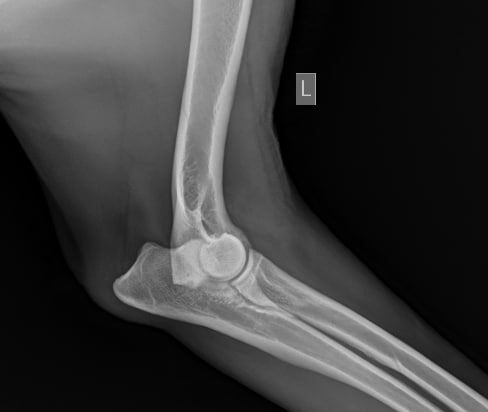

Вот так выглядит артроз локтевого сустава - правый сустав, левый сустав в порядке

Вот так выглядит артроз локтевого сустава - правый сустав, левый сустав в порядке.